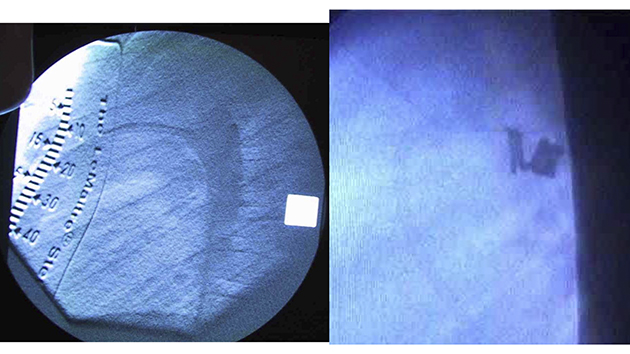

急ごしらえの臨時カテ室

このころ、モンゴル国立母子保健センターには心臓カテーテル血管造影室がなかったので、第1回から第3回渡航の前半は、手術室の窓に暗幕を張り、ポータブルの透視装置を持ち込んで臨時カテ室にしました。

撮影して画像を残すことができなかったので、皆で覗き込んで、一瞬の画像で判断しました。

第1回渡航のカテ6番目、PDA閉鎖としては5番目症例の実際の画像です。

17カ月、体重10kgの女児のPDAを、8mm-8cm6mm-8cm052コイル2個で閉鎖しました。